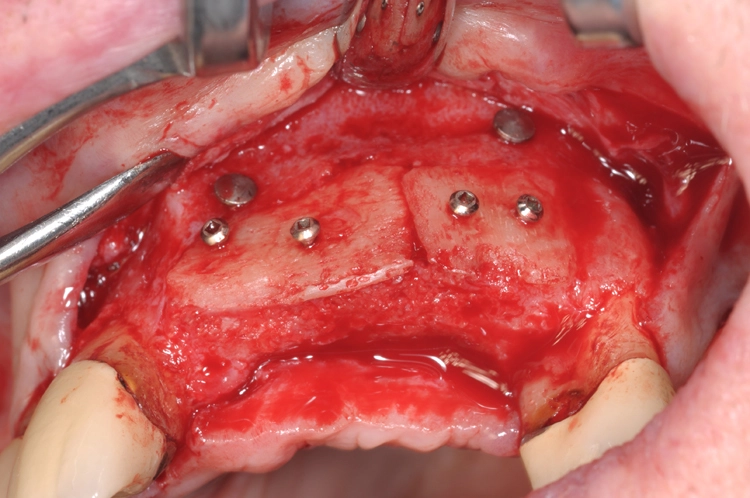

Nach einer viermonatigen Einheilphase erfolgte die Implantation von zwei Straumann® BLT Implantaten mit einer Länge von 12 mm und einem Durchmesser von 4,1 mm im Bereich des aufgebauten Knochens (Ausgangssituation siehe Abb. 8). Vor der Implantation fand vorbereitend eine Glättung der Oberfl äche statt, um scharfe Kanten zu beseitigen (Abb. 9). Für die korrekte prothetische Positionierung der Implantate kamen individuell gefertigte Orientierungsschablonen zum Einsatz, anschließend wurden die Implantate für eine verschraubte Brücke gesetzt (Abb. 10).

Die Abbildungen 11 und 12 dokumentieren das augmentative Relining, das zum Schutz vor Resorption und zur Konturaugmentation dienen soll. Dabei wurde eine Schicht bovines Knochenersatzmaterial (Straumann® XenoGraft) direkt auf den neu aufgebauten Knochen aufgetragen und mit Hilfe einer Kollagenmembran (Jason® membrane, Straumann) konturiert und vernäht. Damit legt man dem darunterliegenden neu aufgebauten Knochen einen Schutzpanzer an, der ihn einmal mehr vor Resorption schützt und die weitere Regeneration begünstigt.